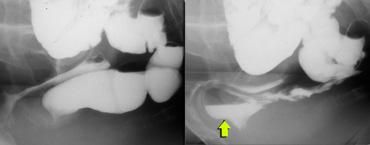

Hình ảnh bình thường khi nghỉ (bên trái); trong khi đại tiện có túi sa trực tràng bị đẩy xuống dưới bởi thoát vị ruột non.

Đôi khi thoát vị ruột non chỉ được xác định vào cuối quá trình đại tiện, sau nhiều lần rặn.

Thoát vị ruột non có thể bị đẩy về phía cửa âm đạo.

Nếu có túi sa trực tràng kèm theo, túi sa này có thể bị đẩy xuống dưới bởi thoát vị ruột non và cuối cùng được tống ra ngoài (hình).